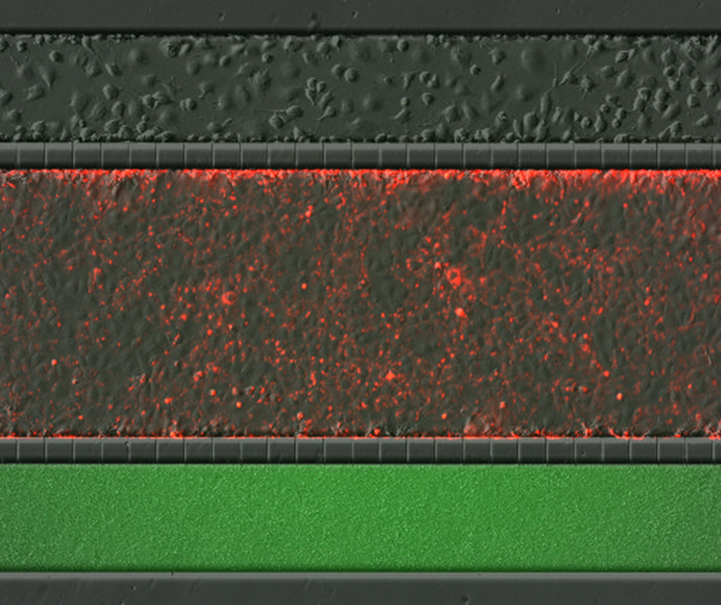

Project 2: Gut Brain Axis on a Chip

This study aims to create a physiologically relevant model to mimic the impact of the gut microbiome on the gut-brain axis using a microfluidic chip. To achieve this, we have established a triculture system comprising epithelial cells, forming the intestinal layer, bacteria representative of the gut microbiome situated on one side of the epithelial layer, and sensory neurons on the opposite side of the epithelial layer. The approach involves developing the microenvironment to replicate the intricate interactions between the gut microbiota and the elements of the gut-brain axis. This chip provides a controlled and dynamic environment to investigate the complex interplay between the gut microbiome and neurological processes, offering insights into the potential implications for gut-brain communication in health and disease.